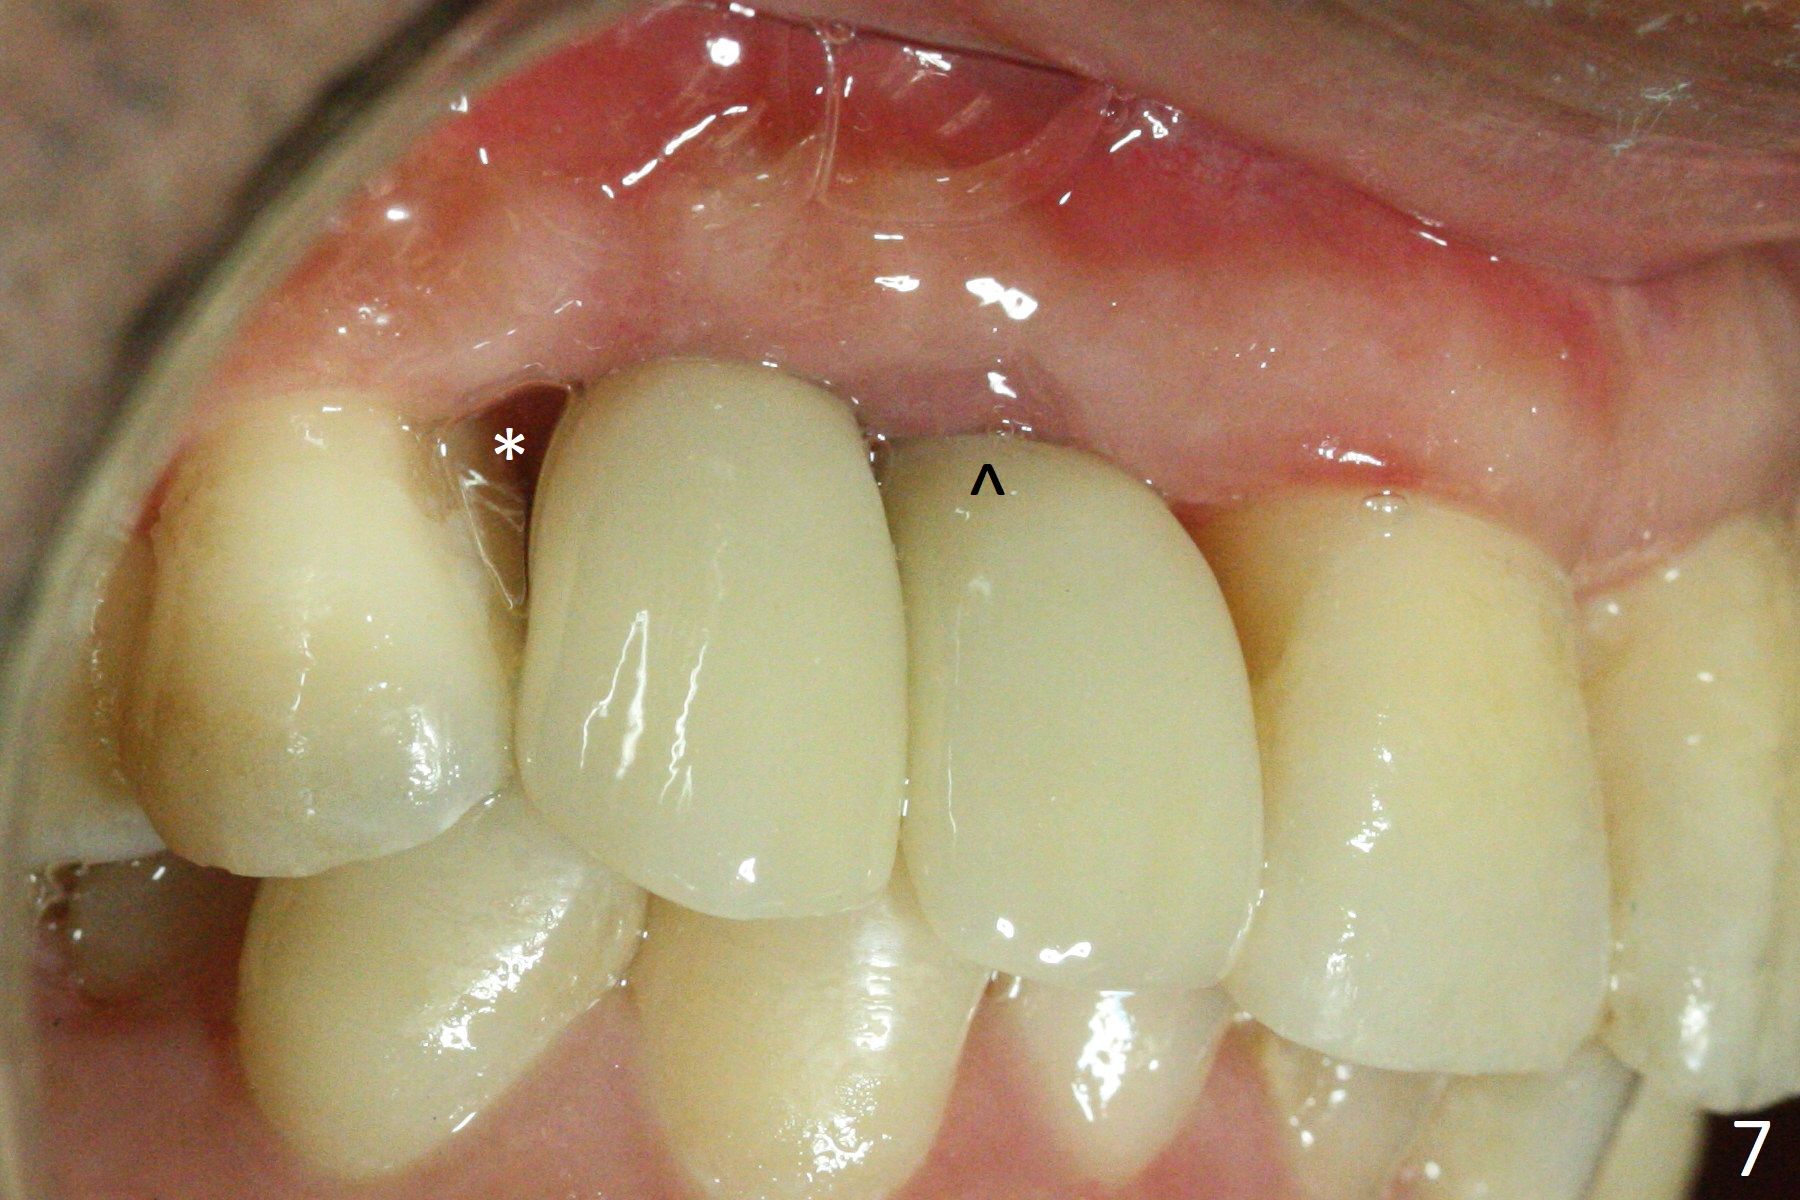

There is no bone loss 3 months postop (Fig.3). After reprep (Fig.4), shades are selected for the final crowns (Fig.5). Before crown cementation at #6 and 7, the patient notes asymmetry with the teeth on the other side (Fig.6). Our concerns are the lack of the papilla distal to #6 (Fig.7 * (multiple modification of provisional needed)) and slight inflammation due to insufficient oral hygiene (^).